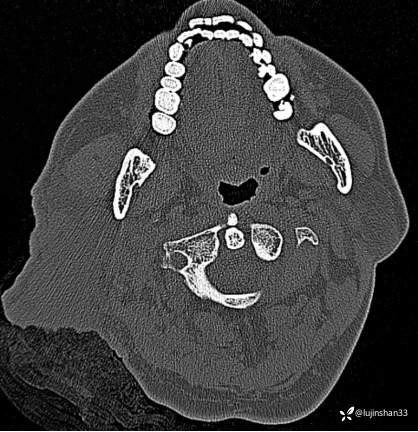

(2023-02-17 17:52,本院)行CT(血管心脏)检查提示:1、右侧耳颞部异常改变,考虑血管瘤可能,可见粗大供血动脉及引流静脉,局部动静脉瘘可能,右侧颈外动脉分支增粗,请结合临床及相关检查。2、左侧颈内动脉粥样硬化,管腔轻微狭窄,请结合临床。血管外科会诊意见:CTA示右颈外动脉起始部结扎后闭塞,介入栓塞暂无合适入路;

临床诊断:耳廓、颞骨蔓状血管瘤合并出血